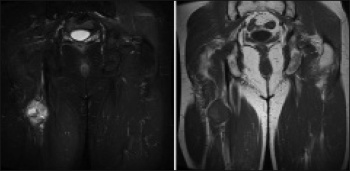

Figure 3. Corresponding coronal T1 and T2 weighted MRI confirmed ultrasound findings of a PNST of the sciatic nerve. Patient had subsequent staging CT of thorax, abdomen and pelvis

Figure 3. Corresponding coronal T1 and T2 weighted MRI confirmed ultrasound findings of a PNST of the sciatic nerve. Patient had subsequent staging CT of thorax, abdomen and pelvis(click to enlarge)